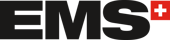

Houston, USA: Pacienti, kteří trpí ztrátou kosti dolní čelisti zapříčiněnou rakovinou, infekcí, úrazem nebo vrozeným onemocněním, žijí s kostními defekty, jež jsou esteticky a funkčně problematické. Vědci z univerzity v Rice vyvinuli techniku vytváření tkáně přizpůsobené konkrétnímu defektu: spočívá v implantování 3D tištěného bioreaktoru do žebra. Kmenové buňky a krevní cévy z žebra vrostou do přirozeného kostního materiálu, který je přizpůsoben pacientovi a může být transplantován do dolní čelisti.

Cílem výzkumu bylo zdokonalit kraniofaciální rekonstrukci využitím přirozených hojivých schopností těla. Tato technika byla vyvinuta proto, aby nahradila současné techniky rekonstrukce, které využívají autogenních kostních štěpů odebraných z různých oblastí, jako je dolní končetina, kyčle a rameno.